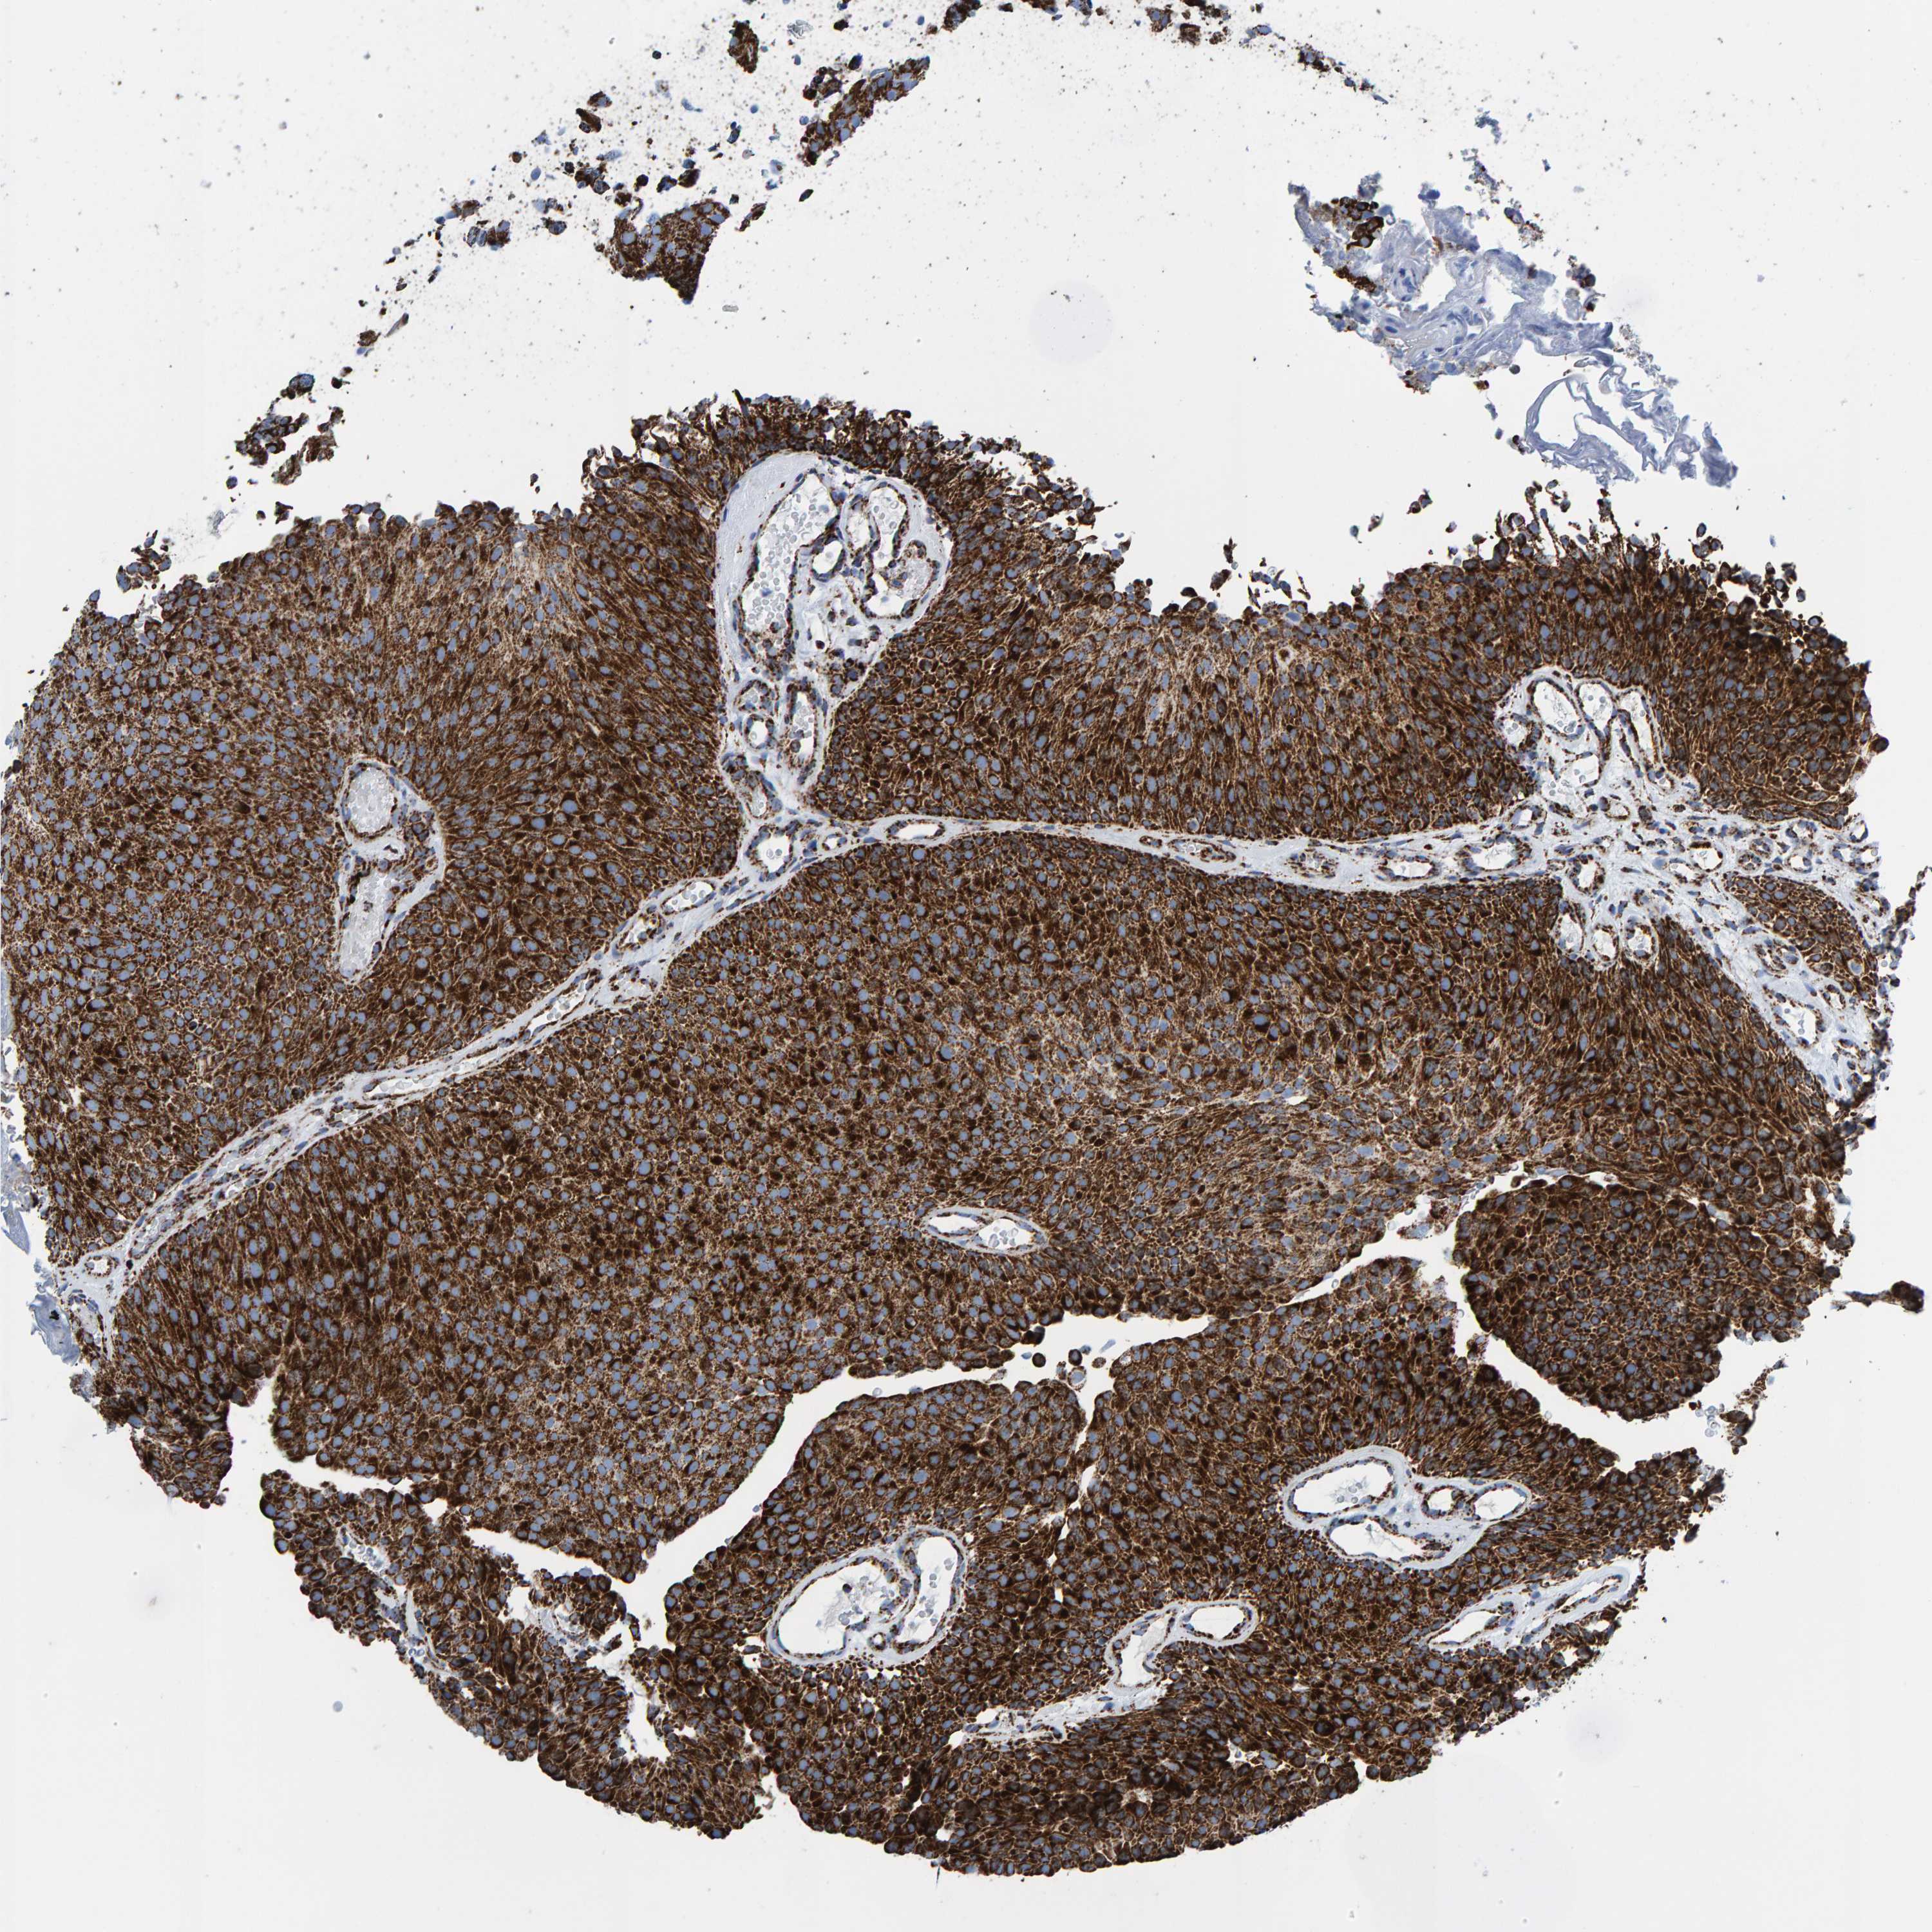

UROTHELIAL CANCER - Protein expressioni

A mouse-over function shows sample information and annotation data. Click on an image to view it in a full screen mode. Samples can be filtered based on level of antibody staining by selecting one or several of the following categories: high, medium, low and not detected. The assay and annotation is described here.

Note that samples used for immunohistochemistry by the Human Protein Atlas do not correspond to samples in the TCGA dataset.

Antibody stainingi

Antibody staining in the annotated cell types in the current human tissue is reported as not detected, low, medium, or high, based on conventional immunohistochemistry profiling in selected tissues. This score is based on the combination of the staining intensity and fraction of stained cells.

Each image is clickable and will lead to virtual microscopy that enables deeper exploration of all samples and also displays staining intensity scores, fraction scores and subcellular localization as well as patient and tissue information for each sample.

Antibody HPA022853

Antibody HPA023043

Antibody HPA023048

Staining

High

Medium

Low

Not detected

Intensity

Strong

Moderate

Weak

Negative

Quantity

>75%

75%-25%

<25%

None

Location

Nuclear

Cytoplasmic/membranous

Cytoplasmic/membranous,nuclear

Urothelial carcinoma, Low grade

Urothelial carcinoma, High grade